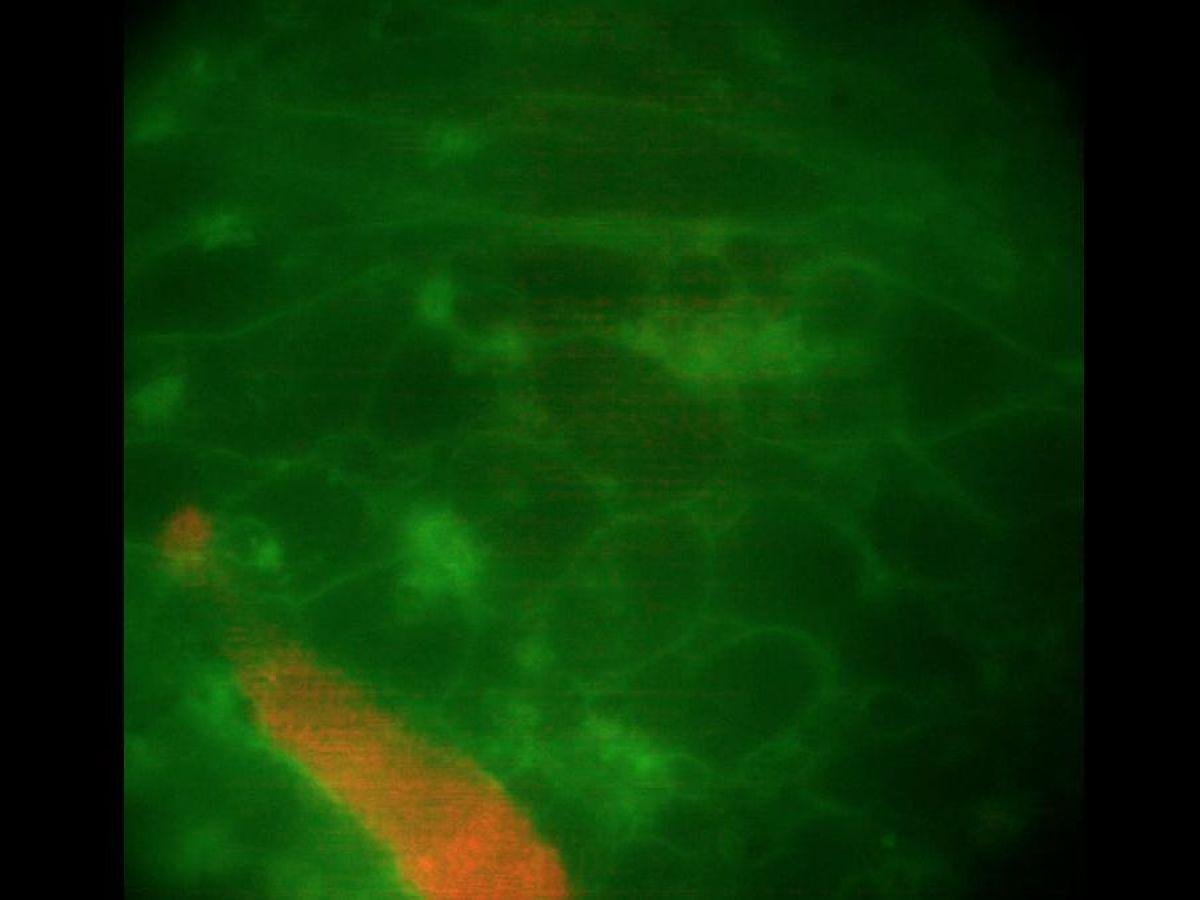

C’est une première : des scientifiques américains sont parvenus à créer en laboratoire à partir de cellules souches des organoïdes capables de développer l’anomalie la plus fréquente du trouble du rythme cardiaque, la fibrillation auriculaire. Cette avancée pourrait permettre de développer de nouveaux traitements face à une maladie qui concerne près de 60 millions de personnes dans le monde.[Lire l'article en intégralité]